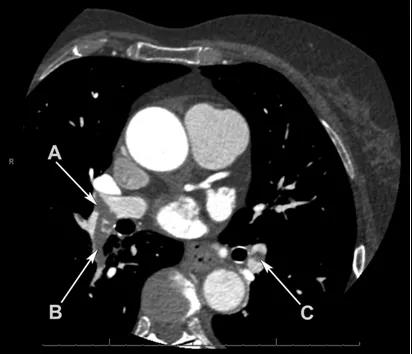

一名73歲的女性因不典型性胸痛來就診,患者無心血管疾病病史,無其余特殊相關體征和癥狀。作為常規檢查,在胸痛診療中心給患者做了冠脈CTA。動脈相的冠脈CTA可見右肺動脈主干遠端,右下葉肺動脈,左下葉肺動脈有彌漫性的低密度灶。冠脈無異常發現。盡管該檢查并非肺動脈栓塞的首選影像手段,但影像學結果能夠將病人診斷為彌漫性雙側肺動脈栓塞。因此最終診斷為彌漫性雙側肺動脈栓塞。

動脈相的冠脈CTA可見右肺動脈主干遠端,右下葉肺動脈,左下葉肺動脈有彌漫性的低密度灶